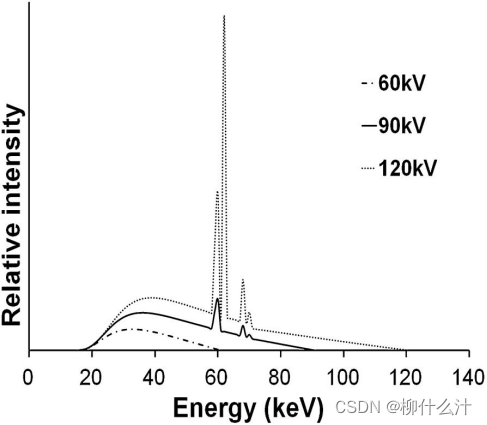

从x光线发射管发射的光束是多能的,由能量沿连续光谱变化的光子组成。诊断性的x射线光谱有一个连续的形状,有几个尖锐的特征峰。

x射线束中的大部分光子是一种叫做制动辐射(Bremsstrahlung)的效应的结果,当从阴极释放并加速向阳极移动的电子与阳极材料发生相互作用是,这种效应就会在x射线管中产生,该材料在一定程度上减缓了电子的速度,根据能量守恒定律,电子动能的损失部分被x射线光子的释放所补偿。Bremsstrahlung光谱通过内部(固有)和外部(添加)过滤进行衰减。在离开X射线管之前,X射线光子将与管壳相互作用,在此期间,主要是低能量的光子被吸收。金属片形式的额外过滤被添加,以确保大多数低能量光子不离开管子,因为这些光子有很大的可能性在病人体内被吸收(即它们对病人的辐射剂量有贡献,但对放射图像没有贡献),CBCT通常使用铝或铜过滤。除了减少入口曝光外,高度过滤的x光线受光束硬化的影响较小。

X射线光谱中出现的离散峰是特征X射线的结果,当电子束与阳极原子的相互作用导致一个内壳中的电子被射出时,就会发生这种现象。空出的位置由一个外壳的电子填补,导致释放出能量与壳的能量状态之间的差异相对应的光子。因此,这些光子具有特定的能量量子,是阳极材料的特征。